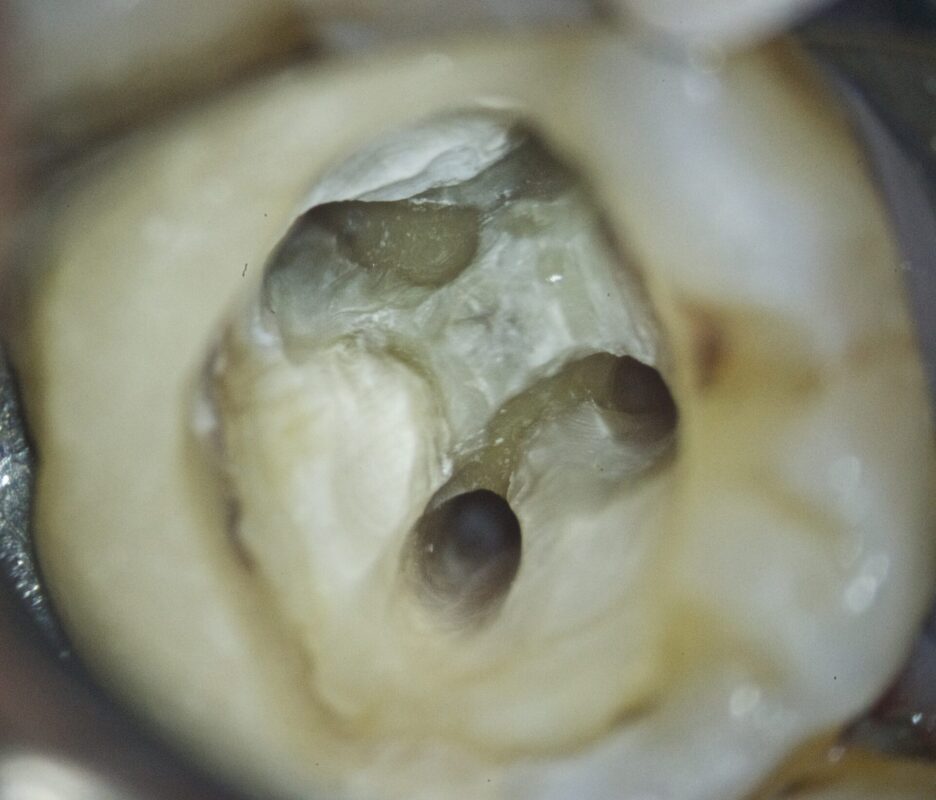

マイクロスコープで見るとこのように見えます。

倍率はおおよそ20倍。

青く染まっているのはう蝕検知液を使用しているからです。

MB2もあるようです。

クラックも入っています。

染色されている部分は汚染されており、健全歯質が確保できず残念ながらこのケースは抜歯となりまし

た。